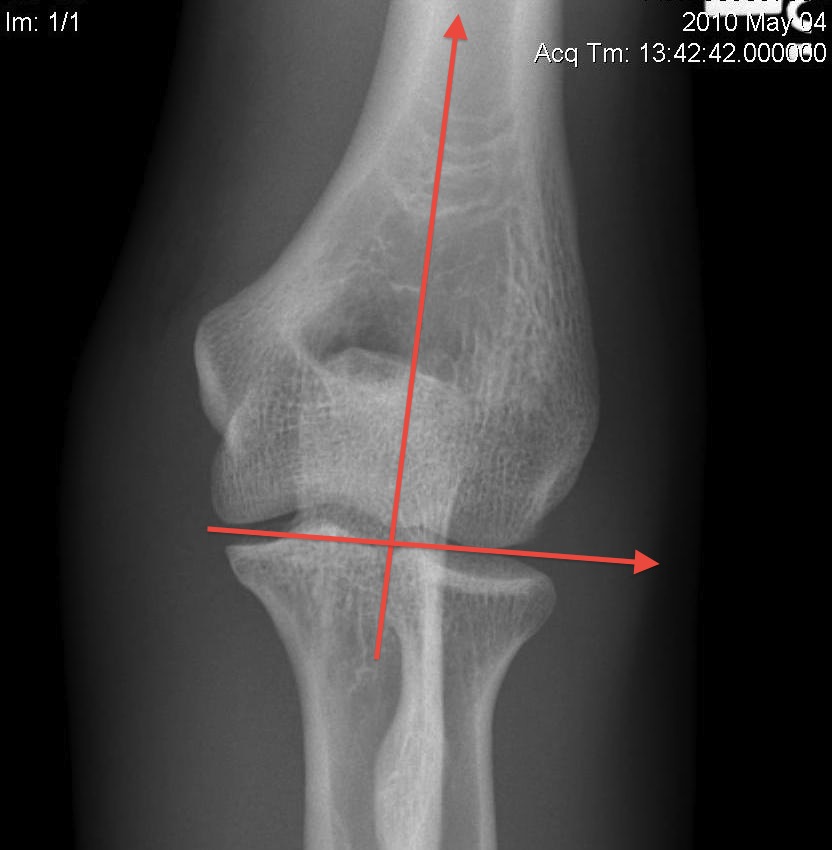

Bony Anatomy

Centre of rotation - trochlea - centre of rotation anterior to humeral shaft |